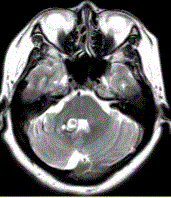

问题 患者女,41岁。头痛半年,加重10d。头部MRI显示如下图。 可能的诊断是(提示MR增强检查如下图。)

选项 A.海绵状血管瘤 B.发育性静脉畸形 C.AVM D.毛细血管扩张症 E.动脉瘤 F.硬脑膜动静脉瘘 G.海绵状血管瘤伴发育性静脉畸形

答案 G